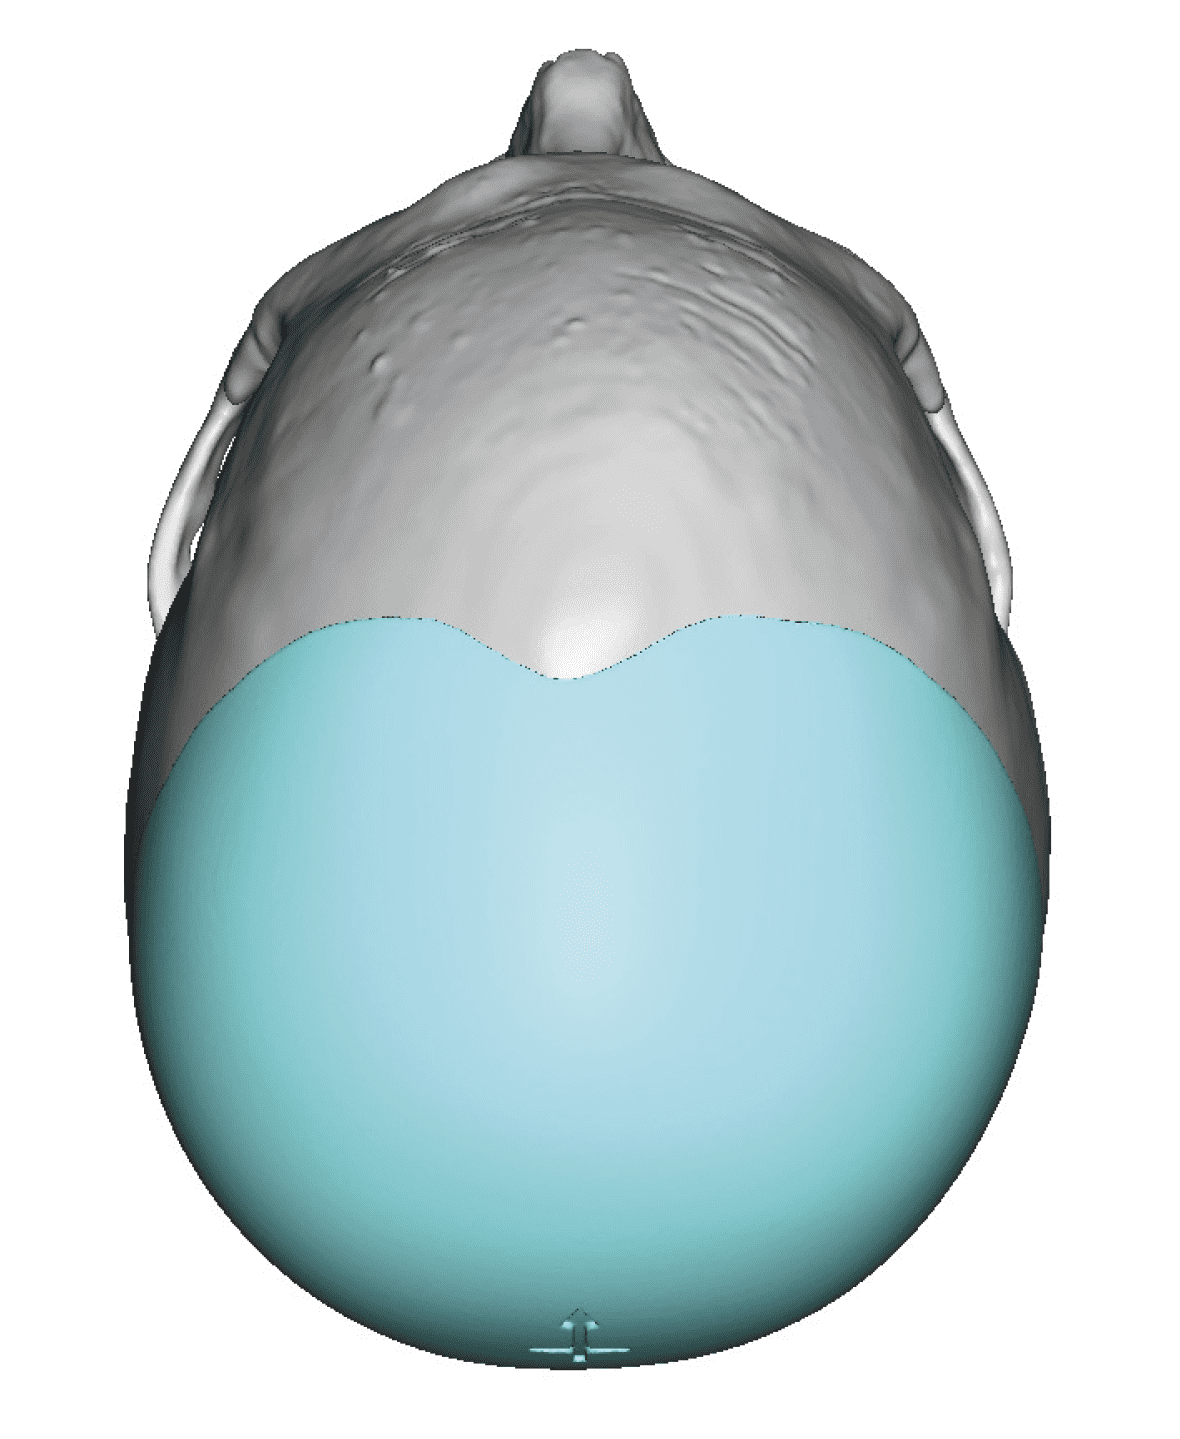

Severe narrowing skull deformity from prior sagittal craniosynostosis repair as an adult.

Complete replacement of entire skull by a custom implant with temporal fat injections.